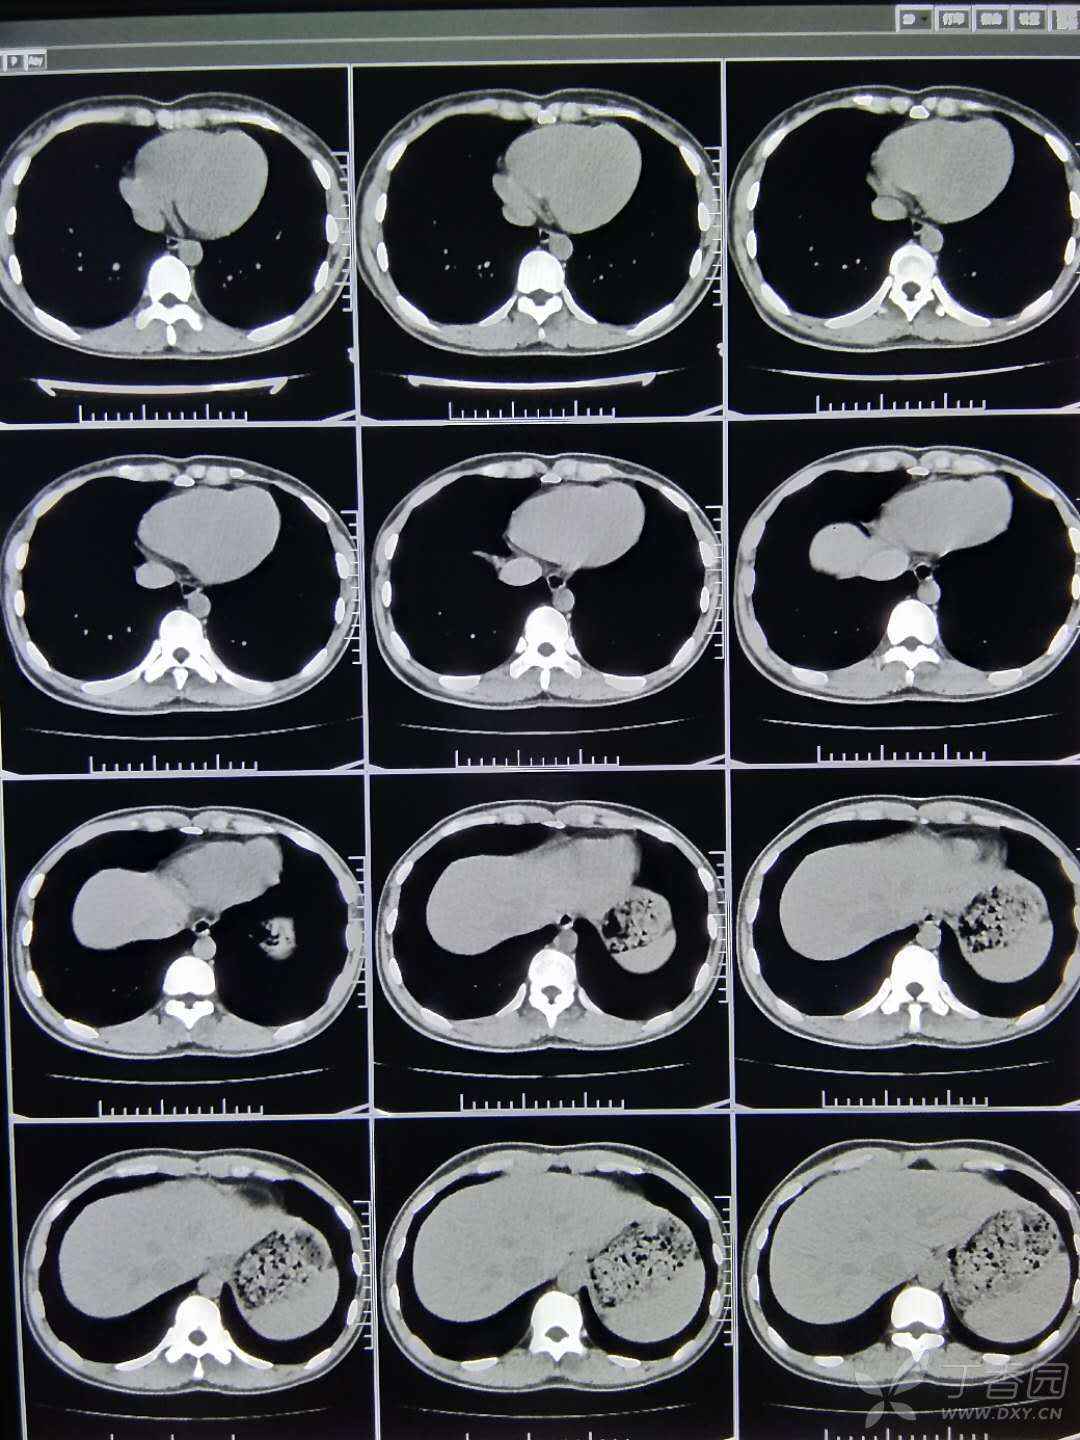

祝福父亲早日康复!

图片尺寸2000x2667